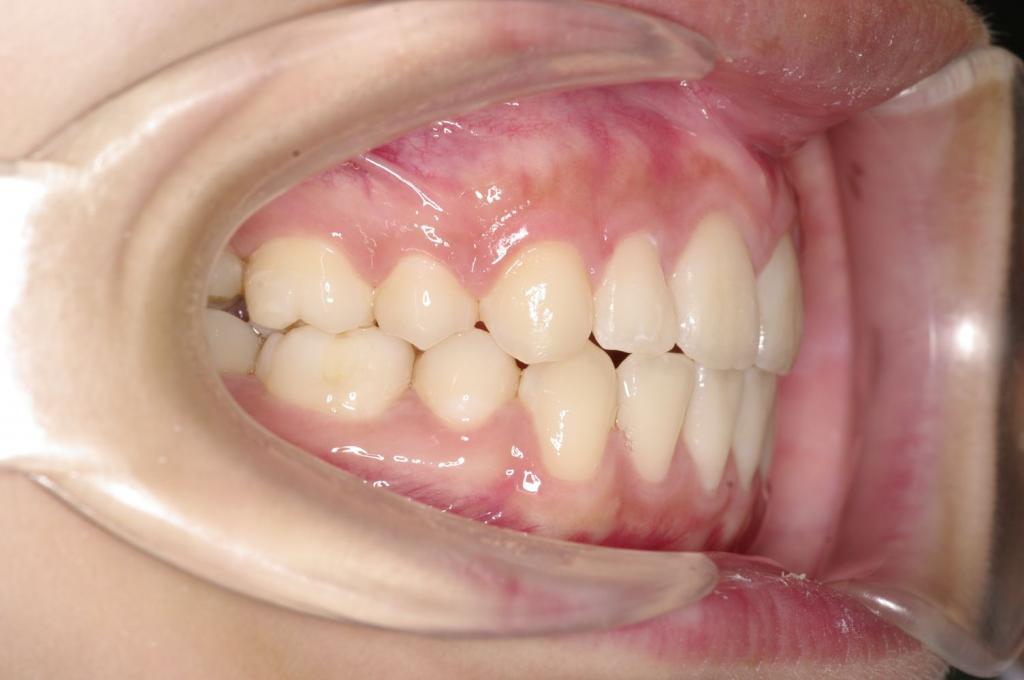

前歯、出っ歯・開咬の矯正治療

(治療期間、治療前後写真、治療方法、費用)WORKS